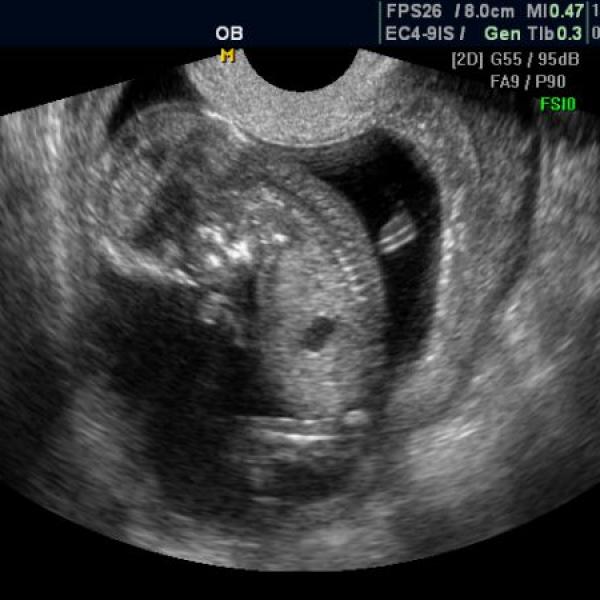

+ ještě přikládám utz ze 10tt